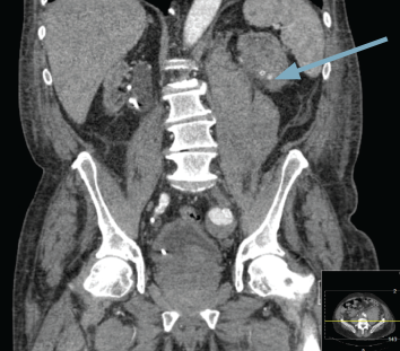

Blush of contrast in left kidney during arterial phase CT.

A percutaneous puncture removed the stent, the radiological nephrostomy tube was removed and a 16F urethral catheter was inserted as a permanent nephrostomy in a patient who was now dialysis dependent (Figure 4). The patient bled post-procedure requiring embolisation (Figure 5).